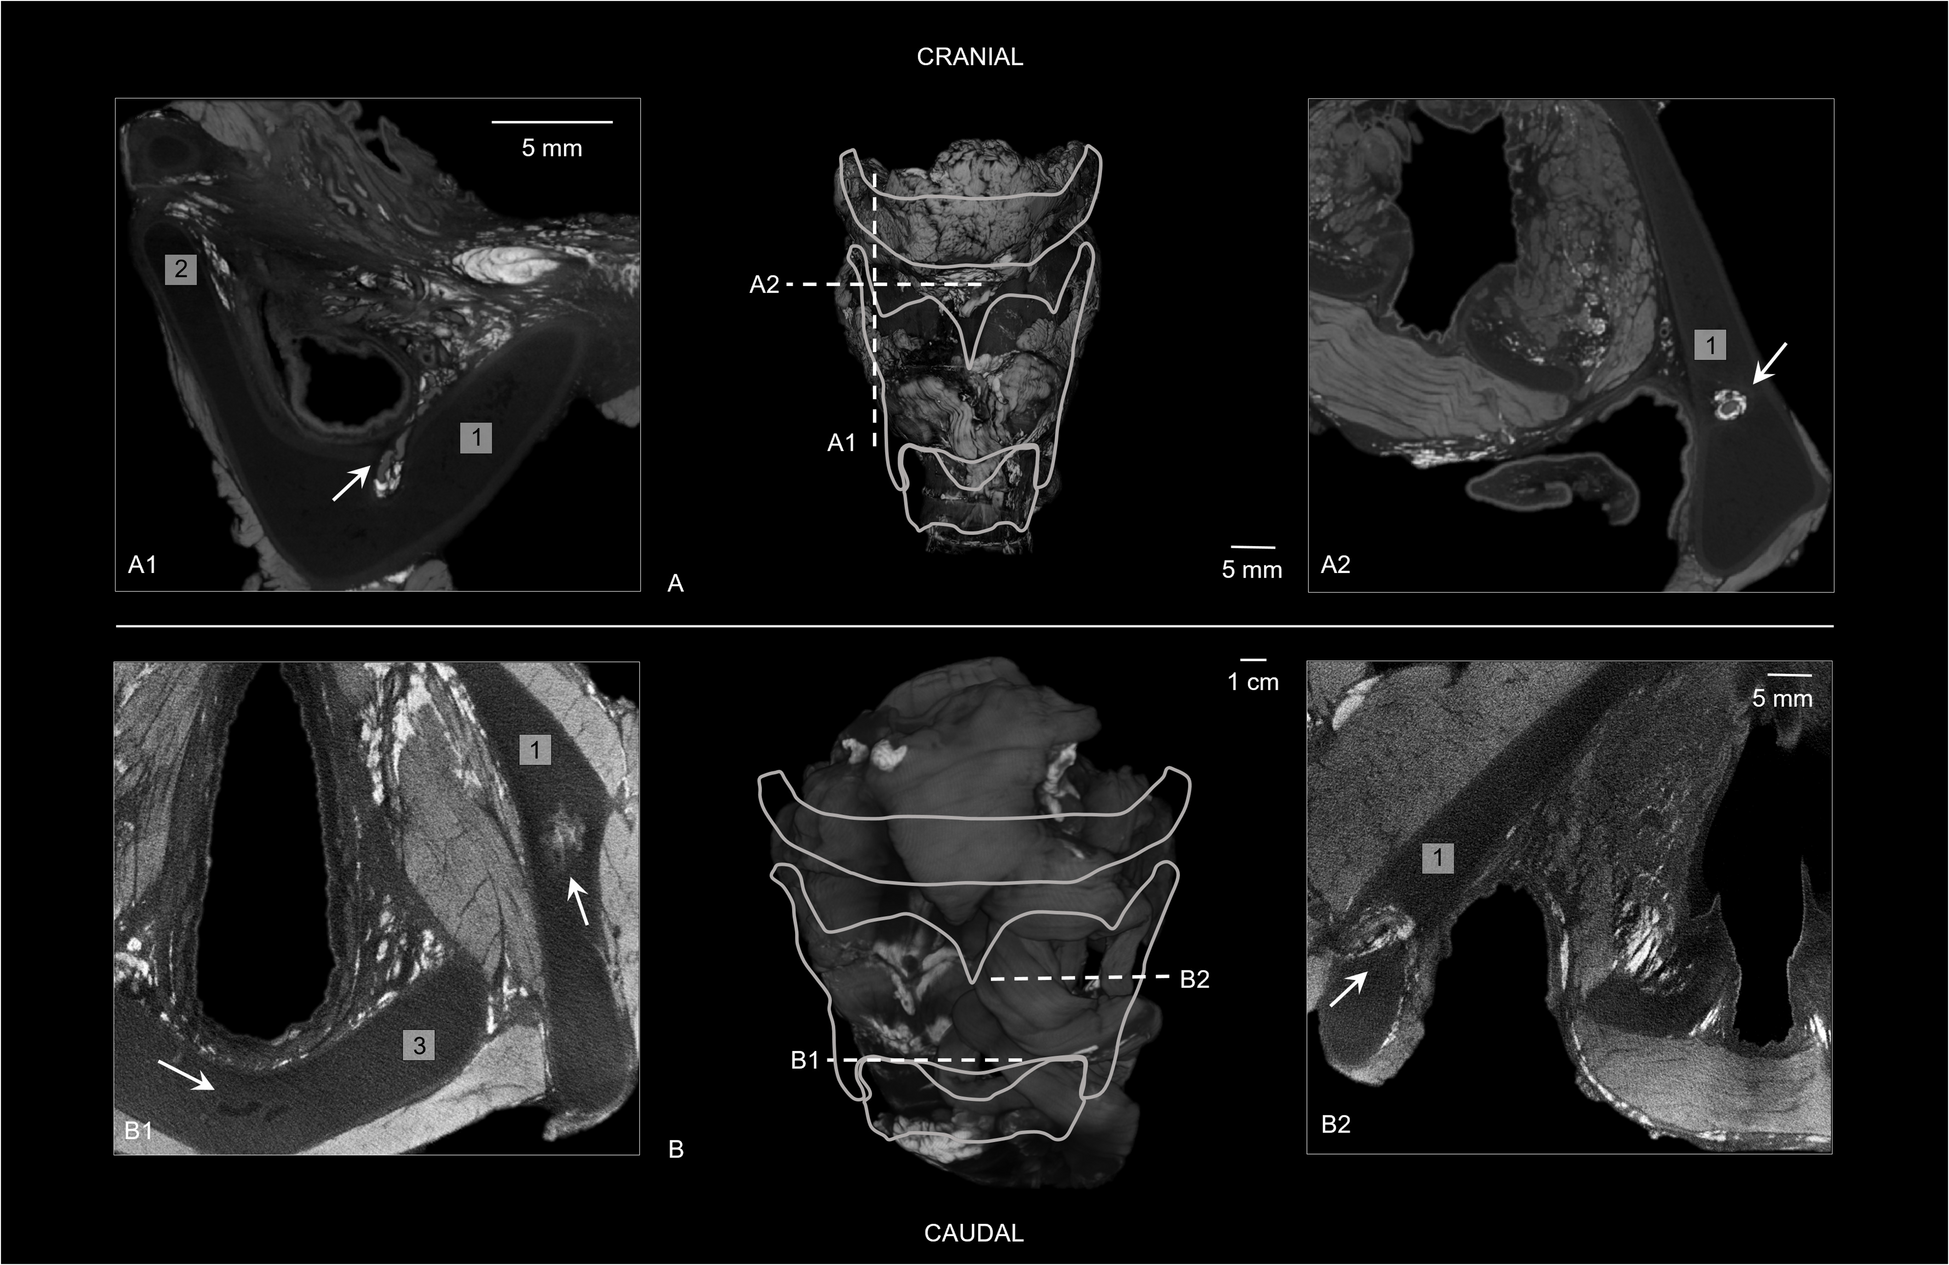

Fig. 4

Thyroid cartilage on diceCT. (a) Frontal view of 3D diceCT volume rendering indicating sections (a1) and (a2) (case 3: 5-year-old male) (25 μm). (a1) Sagittal diceCT section showing a hyperdense bundle (arrow) crossing through the right lamina of the thyroid and a line with higher density was noted encircling the hypodense thyroid cartilage. The opening in the thyroid is also known as the foramen thyroideum. (a2) Transverse diceCT section of the hyperdense bundle with hypodense content (arrow) and a line with higher density was noted encircling the hypodense thyroid cartilage. (b) Frontal view of 3D diceCT volume rendering indicating sections (b1) and (b2) (case 5: 16-year-old male) (35 μm). (b1) Transverse diceCT section of the right lamina of the thyroid and the cricoid cartilage, showing a hyperdense ossification center in the thyroid cartilage (right arrow) and a few hypodense aspects in the cricoid cartilage (left arrow). (b2) Transverse diceCT section showing a hyperdense bundle with hyper- and hypodense content (arrow), crossing through the left lamina of the thyroid. (1) Thyroid cartilage. (2) Superior thyroid horn. (3) Cricoid cartilage

All pediatric hyoid-larynx complexes had a non-fused hyoid bone and normal greater horns (Fig. 3). Samples 1–4 contained bilateral cartilaginous lesser horns and no anomalies regarding the superior thyroid horns. The sample of the 16-year-old (case 5) exhibited a right-side ossified lesser horn, a left-side cartilaginous lesser horn, and bilateral triticeal cartilages. The sample of the 14-year-old (case 4) contained two bone fragments on the stylohyoid ligament. Additionally, samples 3 and 5 showed small circular defects in the lamina of the thyroid cartilage (Fig. 4).

All pediatric specimens demonstrated a non-fused ossified hyoid bone with either bilateral or unilateral cartilaginous lesser horns (Fig. 3). These findings align with known ossification patterns of the hyoid and laryngeal structures, as hyoid ossification starts within the first two living years and calcification of the larynx does not start before the second decade [2]. In addition, literature reports that the calcification of the larynx starts within the inferior thyroid horns and spreads to the superior thyroid horns [2, 4]. Nevertheless, our results show a sample of a 16-year-old male that already showed one calcified center in the thyroid lamina as the beginning of ossification (Fig. 4). This center was identified as an ossification center as Claassen et al. [20] found that the laryngeal ossification pattern consists of a special mode of endochondral ossification, which includes the mineralization of cartilage and creating islands of cartilage before being covered by the deposition of bone. The hyperdense center could represent the mineralized cartilage, as this cartilage appears denser than bone on X-ray images [20].

Furthermore, hypodense features were identified within the cartilages of the hyoid-larynx complex of this 16-year-old (Fig. 4). These features could present part of the ossification process. Dedivitis et al. [21] studied histological aging changes in the cricoid cartilage and showed that adolescents’ cricoid cartilages only consist of typical hyaline cartilage, while the older cartilages showed central areas of lamellar bone tissue and bone marrow cavities filled with adipose and/or hematopoietic tissue. These cavities could possibly be seen as hypodense irregularities in the larynx cartilages on micro-CT.

In two samples, a uni- or bilateral circular defect in the lamina of the thyroid cartilage was observed on micro-CT (Fig. 4). In the literature, this opening is known as the foramen thyroideum (FT) [23]. The FT can occur in one or both laminae of the thyroid cartilage. We found a FT in two of the hyoid-larynx complexes (40%), in one sample unilateral and in the other one bilateral. Previous research reports an incidence of FT in adults of 24–31%, of which 2–11% were found bilaterally [2325]. The prevalences found in this study showed a slight difference in comparison to current literature, which could be due to our small sample size. According to León et al. [25], the adult FT contains a neurovascular bundle in 73%, a nerve branch in 20%, and in 7% only a vascular branch. In our research, diceCT showed a hyperdense bundle within every FT. Within those hyperdense bundles, two hypodense tubular structures could be visualized in one sample, and the other sample showed one hypodense and one hyperdense tubular structure (Fig. 4). Since blood shows hyperdense on diceCT images, we suspect that the hypodense tubular structures are nerves (branch of the superior laryngeal nerve) and the hyperdense structures are blood-filled vascular branches. As neurovascular bundles are surrounded by connective tissue, the hyperdense staining surrounding the bundles is considered connective tissue. This is in line with the hyperdensely stained tissue we discovered in the cricoid area, paraglottic, and pre-epiglottic spaces (Fig. 5). These spaces contain areolar or loose connective tissue, which is composed of adipose tissue with elastic and collagen fibers [22]. Hence, B-Lugol binds to adipose tissue and/or elastic and collagen fibers as well. Anatomical dissection could provide a definitive answer to the content of the FT.